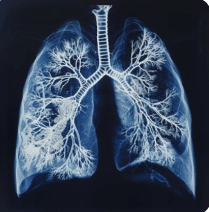

폐 석회화(Calcification of the lung)는 폐 조직 일부에 칼슘이 침착되어 석회화되는 현상을 의미합니다. 일반적으로 건강검진이나 흉부 X-ray, CT 촬영에서 우연히 발견되며, 대개 무증상으로 진행됩니다.

✔ 정기적인 건강검진 – 흉부 X-ray 또는 CT를 통해 진행 상태 확인